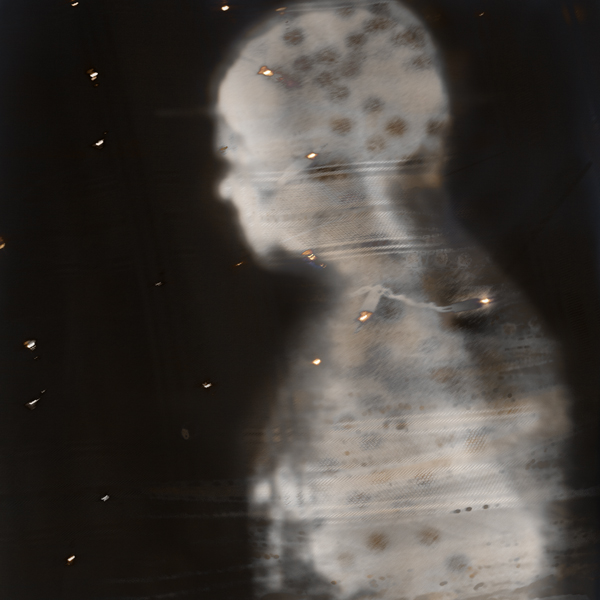

Within these photographs, medical imagery digitally combined with images of fabrics reveal hauntingly ethereal portraits of people when they are their most vulnerable. Alterwitz exposes these emotions with stark bluntness and at other times with tenderness. While the details of the skin and features are blurred, lost in the medical scan, expression can be seen in the tilt of a head, the rise of a chin, the lean of a shoulder. Combined with the layering of fabric images, the result is an eerie enshrouding of faces and figures that addresses notions of loss and remembrance, enlightenment and anger, and life and death. The fabrics, which are typically used to clothe our bodies, are stripped away and blended with the images of our internal organs and structures revealing beauty as it reflects life, contemporary culture, and the intense realities of everyday life, shedding light on the struggles and fears related to being human.